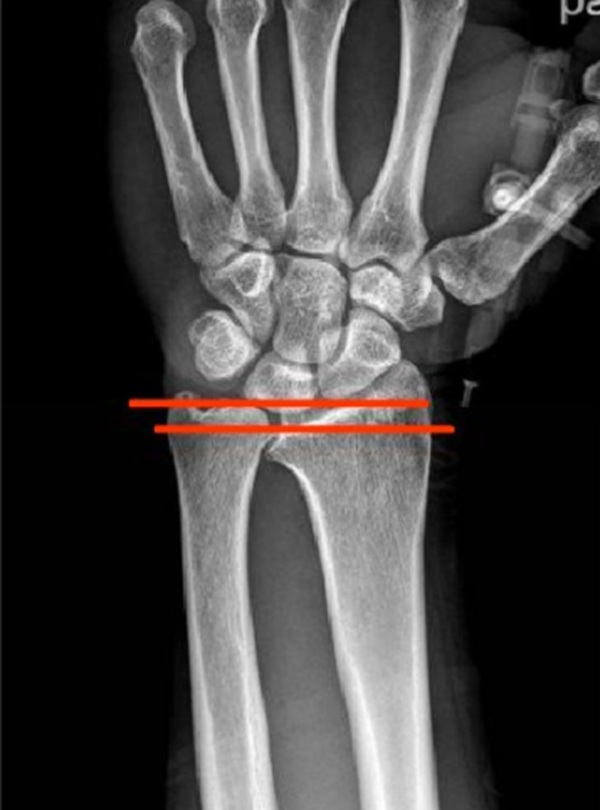

(1)X线 检查尺骨、桡骨直接位置及退化情形,通常无直接征象。

Case1

女性,42岁,右腕疼痛1年+,2020年4月手术。

影像学检查